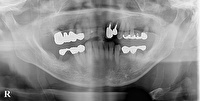

インプラント長期症例

2026-03-01

インプラント

当院で38年前に下顎の左右奥歯に今では珍しい板状のサファイアインプラントを理入しています。38年の間に左下の人工歯の中の自分の歯が虫歯で溶けてしまっていますが動揺も無くアメもバリバリ咬めるそうです。大変喜ばれています。上の歯の治療も同時期に行って今も調子良く食べられています。